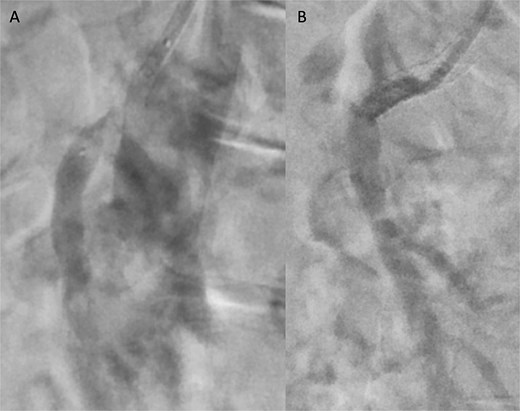

Angiographic images before (A) and after (B) primary stenting of SMA ostium using a 6 × 39 mm Advanta® stent with proximal flare.